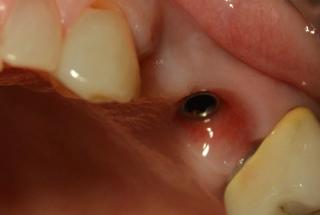

Clinical cases

MPI closely monitors clinical cases in the market to ensure their correct functioning and successful outcome.